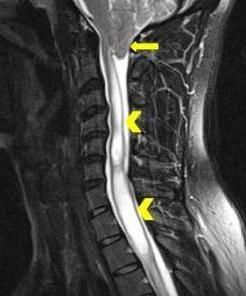

A 29-year-old man presented with a 4-year history of headache and severe neck pain that increased in intensity with coughing, lifting, or exercising. On palpation, there was paraspinal and bony prominence tenderness. No abnormalities were seen on a flexion-extension radiograph of the cervical spine. A cervical MRI scan without contrast revealed a Chiari I malformation with herniation of the cerebellar tonsils measuring up to 2.7 cm (arrow) and extensive syringomyelia (arrowheads).